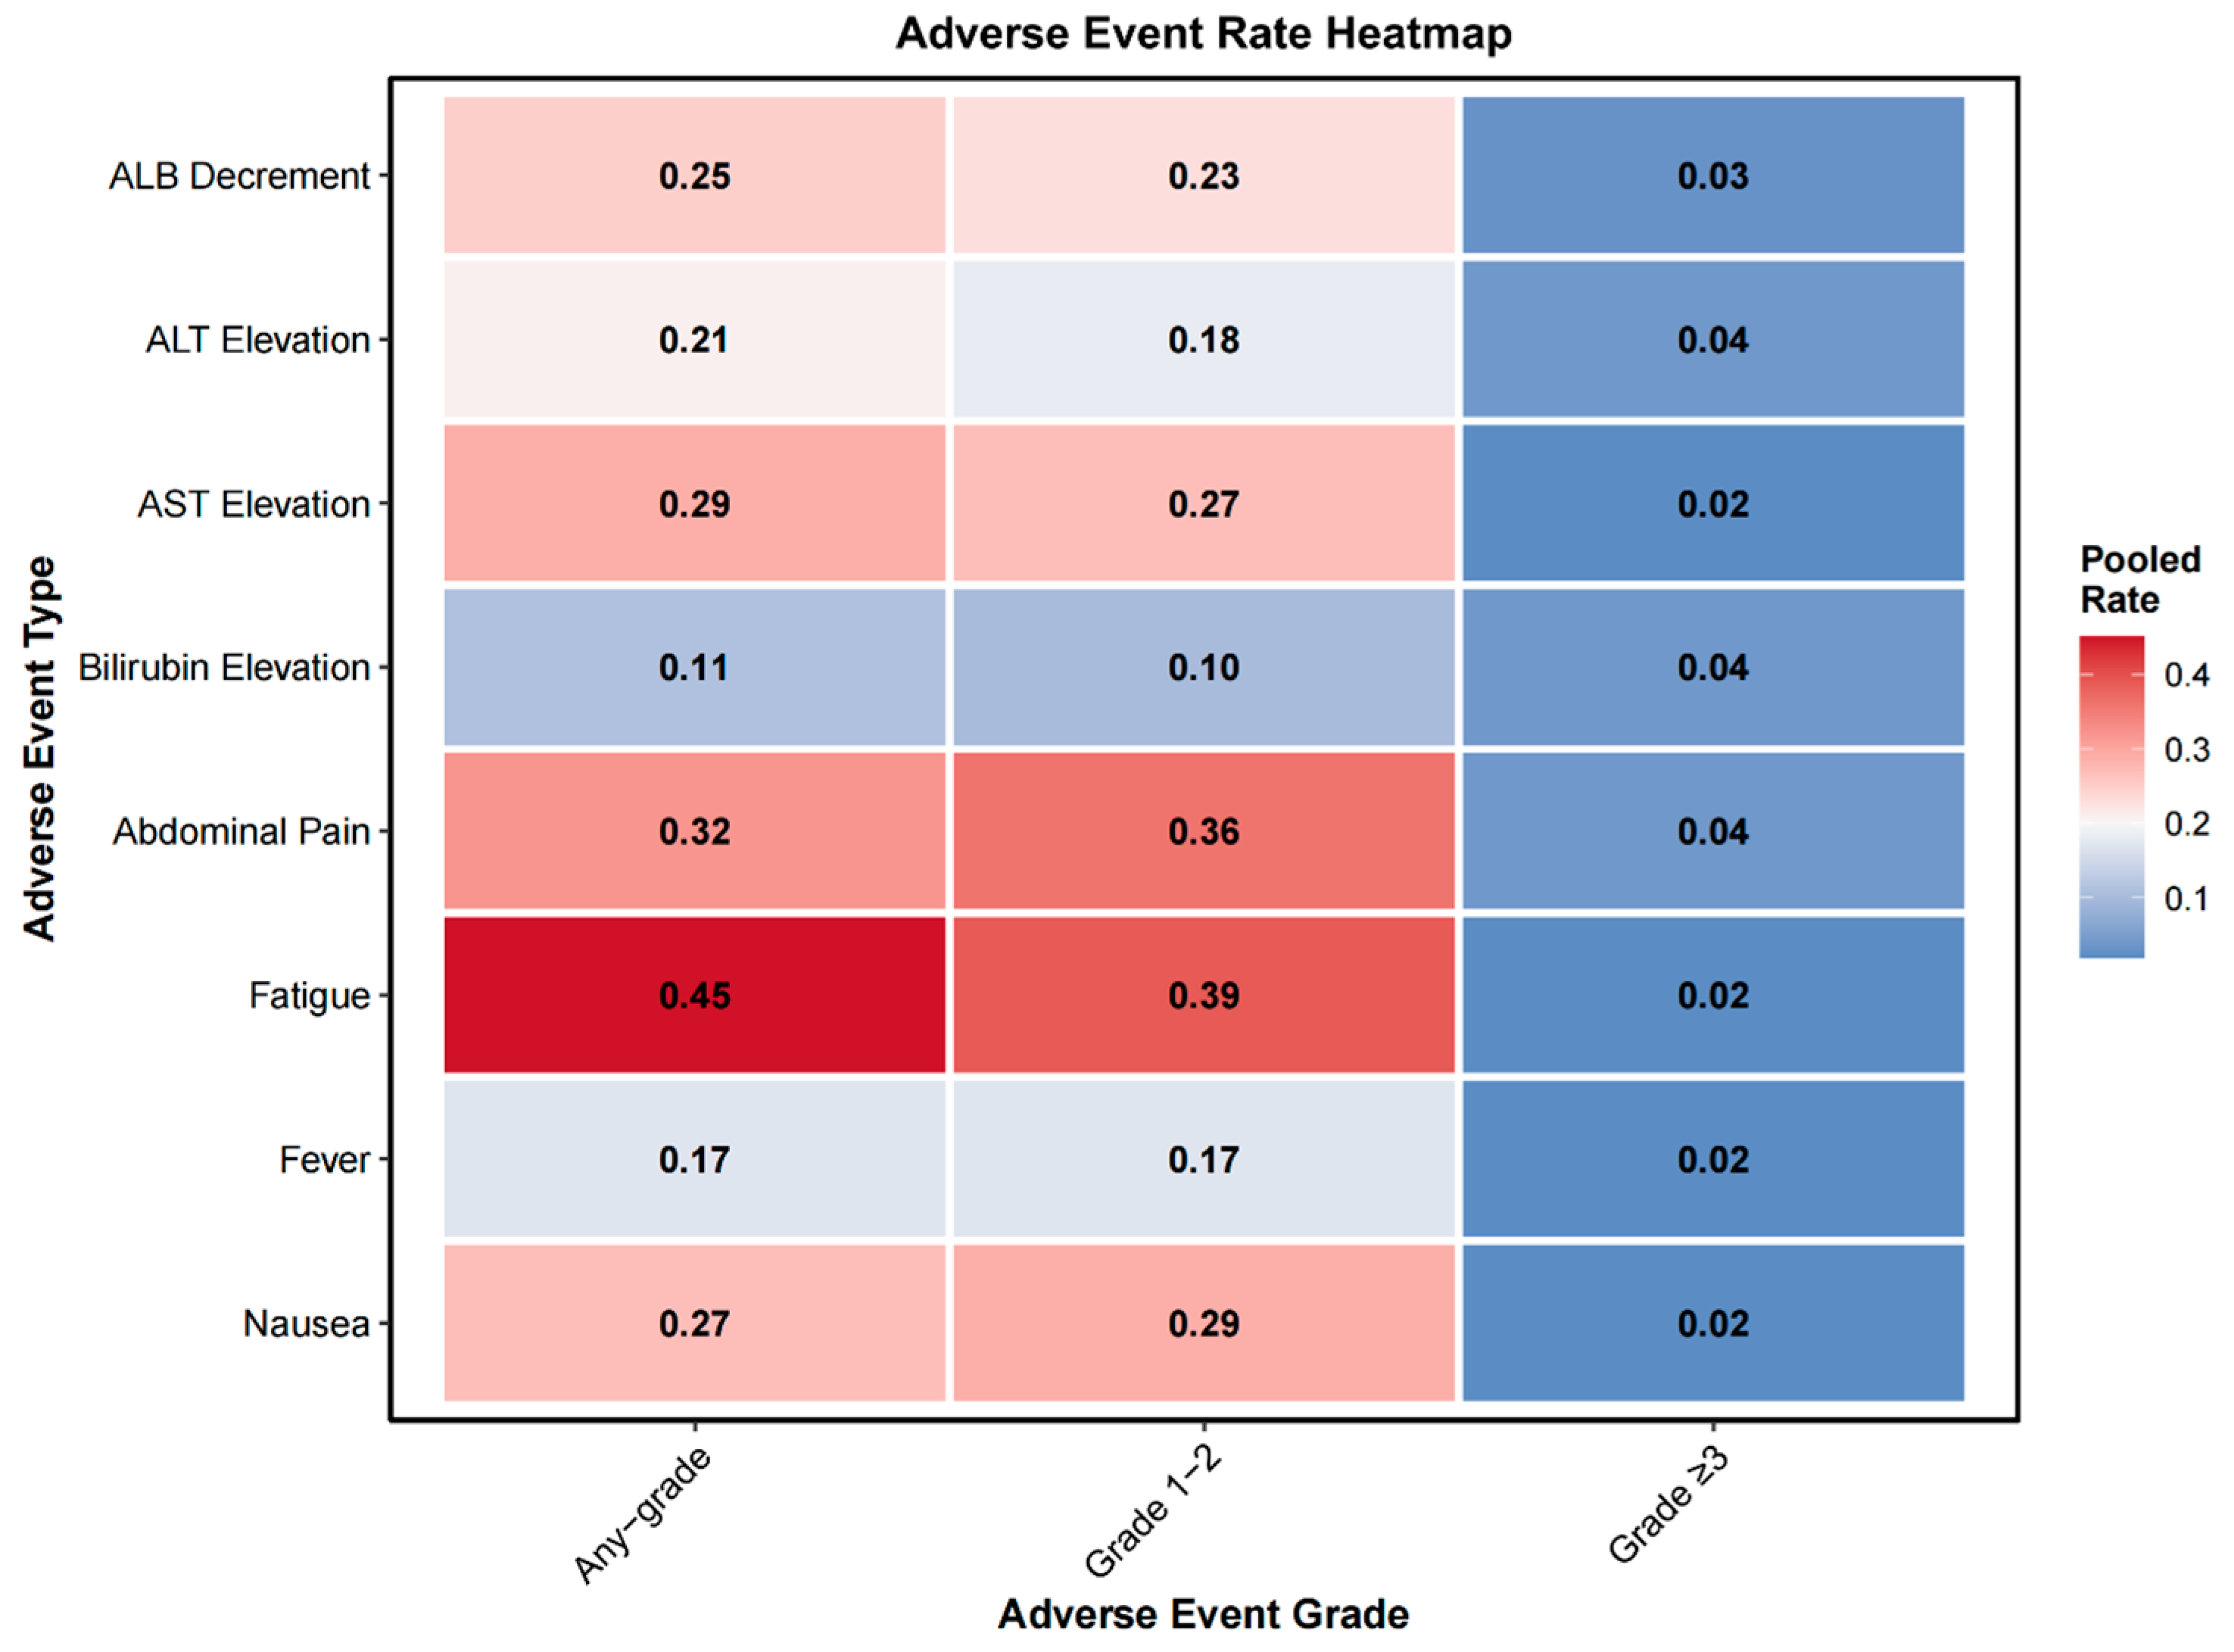

3.2.7. Adverse Events

4.2. Safety